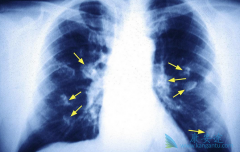

现今社会肺癌的发病率很高,人们不知道是什么原因造成的,对肺癌的知识比较匮乏,只知道谈癌色变。癌症的出现相信大家也有全面的认识,因为是疾病就会给自己的身心照成极大的伤害,因此在面对肺癌的到来时人们更需要选取较好的办法来进行治疗,如果不注 ...

肺癌已经成为癌症之王,许多人到了肺癌晚期才发现,如果要治愈几率渺茫。那么 肺癌晚期的症状 有哪些呢?肺癌晚期有6大症状。由于空气污染、吸烟等因素,肺癌的发病率逐年递增,且在世界范围内,肺癌为最危险的恶性肿瘤之一,其被称为癌中之癌王。据报道 ...

虽然现在已经是一种比较常见的癌症了,大部分的肺癌患者被查出来都是 肺癌晚期 了,晚期已经是很难治愈了的。其实在发现肺癌之前是有一些暗号表示自己已经有肺癌了的,这个时候人们就应该多关注自己的身体,看一下有哪些地方不对劲,如果及时发现是早期 ...

现代随着环境以及工业污染,导致肺癌的发病率非常高,但是人们对肺癌的了解相当少。只是听说得了癌症就等于判了死刑,其实我们应该更理性的看待。因为人一旦生病无论是身体还是心理都会有极大伤害,为此我们在面对癌症的到来更该选择最合适的疗法进行合 ...

肺癌晚期都会出现哪些增加患者痛苦的症状,这些痛苦不仅包括身体上的,还有心理上的,包括焦虑,忧愁,恐惧等,采取措施给减轻患者病痛,给患者心理带来些许安慰,让患者好过一些也是治疗的重要部分。下面给大家介绍 肺癌晚期症状 。疼痛。肺癌引起的疼 ...